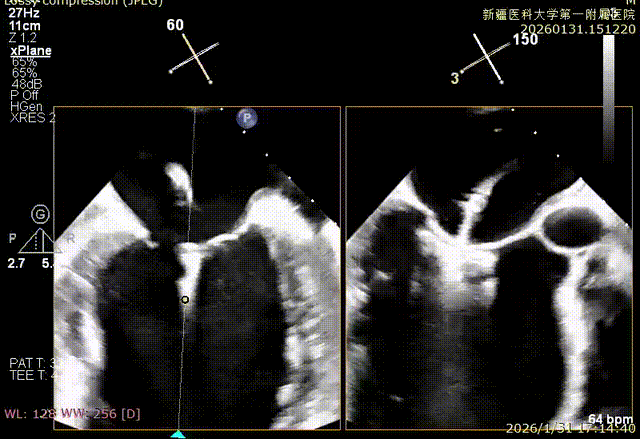

XPLAN切面2区后叶栓系

XPLAN切面中重度反流

XPLAN后叶严重栓系

Bicom切面中重度反流